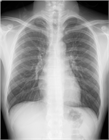

1. 胸部X線写真(CXR)で検出しきれない特発性縦隔気腫が少なからずあるため、CXRが正常範囲と判断されても、特発性縦隔気腫が疑われる場合は、積極的に胸部CTを撮影することを勧める(推奨度2)